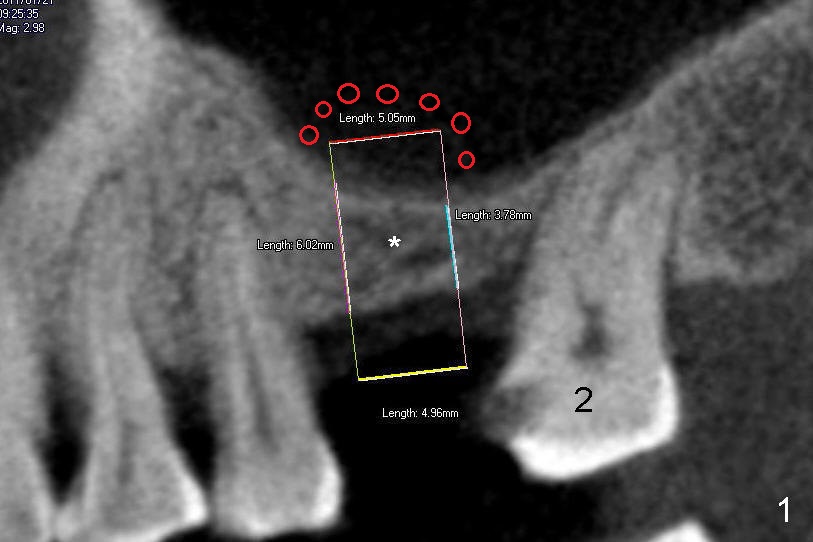

A 60-year-old man has worn an upper partial denture for a while. We are in a process replacing it with implants. Next step is for #3 and then #2. It appears that bone density in the edentulous region (Fig.1 *) is low; the height is also limited (between 3.78 to 6.02 mm). A cylindrical or tapered soft tissue level implant (4.5 or 5x11 mm) is planned (Fig.1,2). Sinus lift is anticipated (red circles in Fig.1,2 (CT sagittal and coronal sections). The drawback associated with the soft tissue level implant is adjustment of the partial following implant placement.

Alternatively, a bone level implant can be used (Fig.3,4). The shortest implant available is 6 mm, but the smallest diameter is 5.9 mm. As the tooth #2 is affected by periodontitis with mesial drifting (Fig.3 arrow), the mesiodistal edentulous space is quite narrow (6.40 mm).